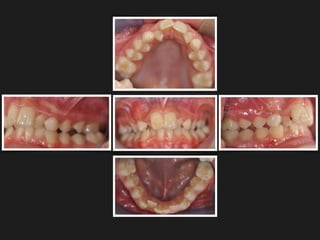

Posterior Crossbite in the mixed dentition is a

common malocclusion, with a prevalence that

varies from 4% to 23%

Phatouros A, Goonewardene MS Morphologic changes of the

palate after rapid maxillary expansion: a 3-dimensional

computed tomography evaluation Am J

OrthodDentofacialOrthop. 2008 Jul;134(1):117-24

Physiological

condition

Posterior

bilateral

unilateral

crossbite

Clinically the relevance of the topic is clear,

since transverse occlusal discrepancies are

relatively common, with uni or bilateral

crossbites, occurring in 9.4 per cent of boys

and 14.1 per cent of girls (Helm, 1968).

The transverse dimension represents the sum

of the skeletal maxillary base and the

inclination of the buccal segment teeth and

surrounding alveolar bone (Solow, 1980).

Discrepancies involving the skeletal base

should be treated by skeletal expansion,

whereas dentoalveolar discrepancies should

be corrected by tooth movement.

Clinically transverse contraction of the

jaws occurs with posterior crossbite

MONOLATERAL BILATERAL